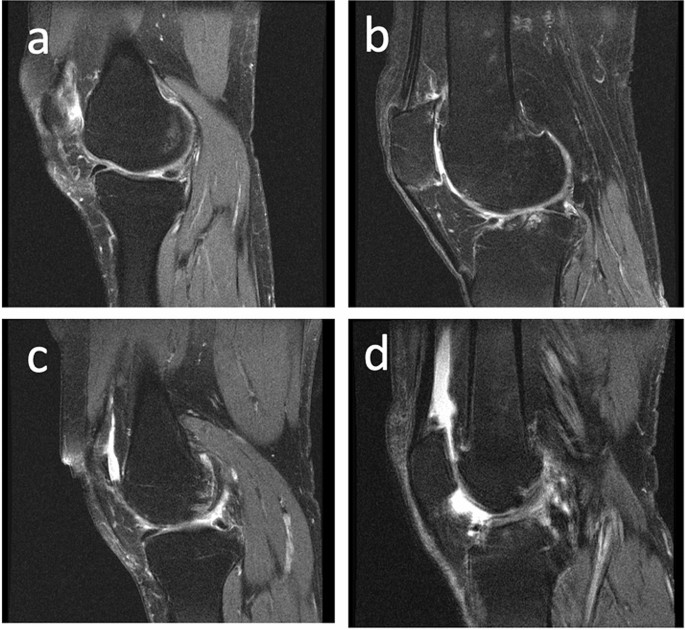

Joint effusion, or accumulation of fluid, is commonly seen in OA patients19. This feature of OA has been associated with increased levels of pain20 and risk of cartilage loss21, demonstrating the importance of accurate assessment of effusion in OA patients. Although the composition of effusion is not well understood, its severity is correlated with the inflammation present and graded as mild, moderate, or severe. While there are multiple methodologies for quantitatively assessing effusion severity19, one commonly used metric is the MRI Osteoarthritis Knee Score (MOAKS) effusion-synovitis score22. This metric takes into account the fluid equivalent signal within the joint cavity on images with T2-, intermediate-, or proton-density-weighted contrast including synovitis and effusion and therefore uses the term effusion-synovitis, and will be referred to as MOAKS-ES in this work for brevity. This is scored on a scale of 0–3, with 0 being a physiologic amount, 1 being small (fluid continuous in the retropatellar space), 2 being medium (with slight convexity of the suprapatellar bursa), and 3 being large (with evidence of capsular distention). Examples of sagittal TSE images with each of these grades are shown in Fig. 1. This methodology has been used in several studies, including using data from the Osteoarthritis Initiative (OAI), a large multi-center study evaluating close to 5,000 OA patients23,24. However, this assessment often requires manual evaluation by a radiologist of a high-resolution image in the axial plane, which can become a laborious process for large patient volumes. Furthermore, such assessment can result in substantial inter- and intra-rater disagreements22. Additionally, several benefits would result from enabling effusion grading based on low-resolution images. A lower-resolution scan, employing fewer phase encodes, would shorten the scan, improving the patient experience and potentially increasing scanner throughput. Low-resolution processing also has value when using low-field MRI devices. This technique has seen substantial development in recent years and allows low-cost medical imaging in settings not applicable for conventional scanners, but typically acquires lower-resolution data25,26,27,28,29. There is therefore an unmet need for automating effusion estimation from MR images, including from images acquired non-axially with a low resolution.

Examples of subjects with (a) Normal knee (MOAKS score 0), (b) Small effusion (MOAKS score 1), (c) Medium effusion (MOAKS score 2), and (d) Large (MOAKS score 3) effusion. In this work, a binary classification is used, with images as in panel (a) classified as without effusion, while images as in panels (b–d) are classified as with effusion.